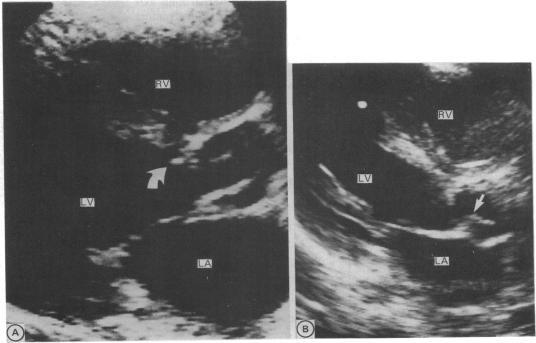

Retrospective echocardiographic review identified 58 consecutive infants and children with fixed subaortic stenosis. Mean (SD) age at diagnosis was 4.8 (3.6) years (range two days to 14.7 years), and diagnosis occurred in infancy in eight. Associated cardiac abnormalities were present in 41 (71%) whereas fixed subaortic stenosis was an isolated lesion in 17 (29%). Four types of fixed subaortic stenosis were identified: short segment (47 (81%)), long segment (7 (12%)), posterior displacement of the infundibular septum with additional discrete narrowing of the left ventricular outflow tract (3 (5%)), and redundant tissue arising from the membranous septum (1 (2%)). Echocardiographic studies had been performed before the diagnosis of fixed subaortic stenosis in nine patients, all with associated abnormalities. These were performed in infancy in each and showed a "normal" left ventricular outflow tract in six and posterior deviation of the infundibular septum in three. In 16 patients serial echocardiographic studies had been performed after the diagnosis of fixed subaortic stenosis but before surgery of the left ventricular outflow tract. Rapid evolution of short segment to long segment narrowing was seen in one patient, and tethering of the aortic valve or mitral valve developed in a further four patients. Aortic valve or mitral valve involvement was not seen before the age of three years but was common thereafter (10/40 patients, 25%). Fixed subaortic stenosis may be an "acquired" lesion with the potential for changes in form as well as progression in severity of left ventricular outflow tract obstruction.